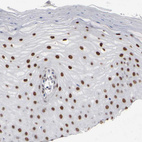

Immunohistochemical staining of human skin shows moderate to strong nuclear positivity in squamous epithelial cells.